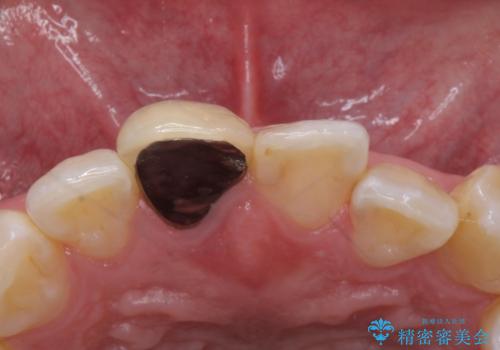

- 前歯のかぶせ物の色が気になるとのことで来院された患者様です。

セラミッククラウンで作り変えていきます。

色・形ともに改善され、大変喜んでいただけました。